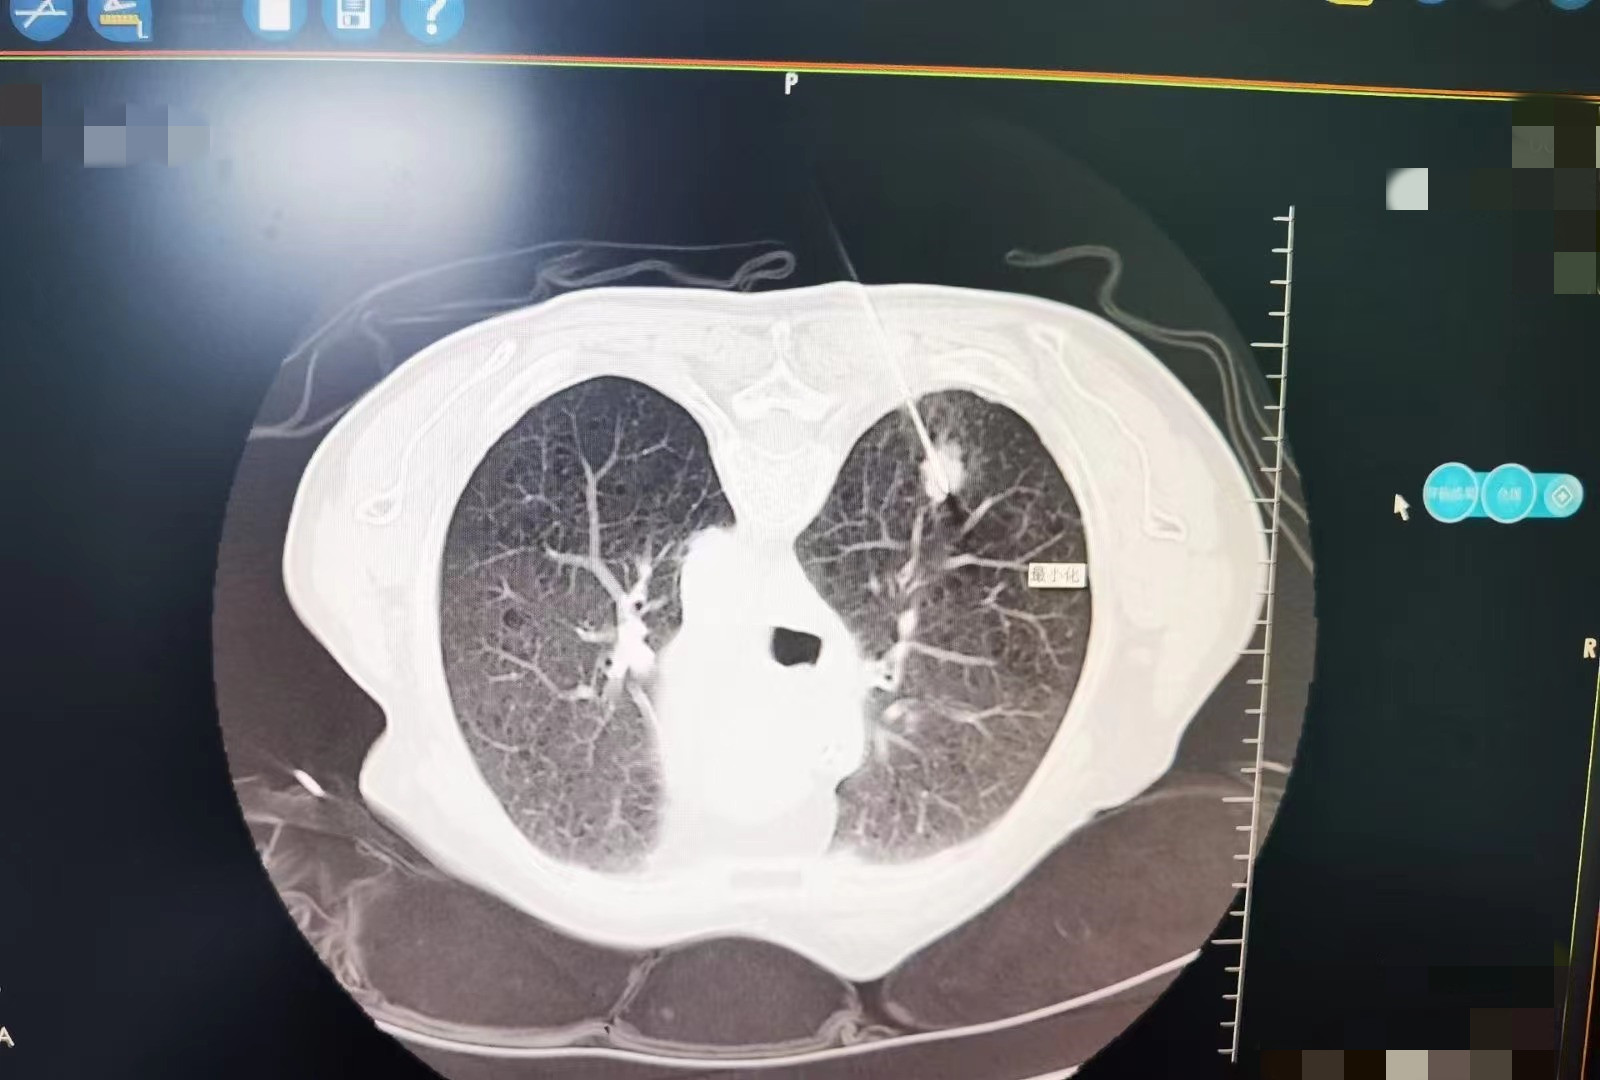

小细胞肺癌肺内转移,冷消融病灶坏死